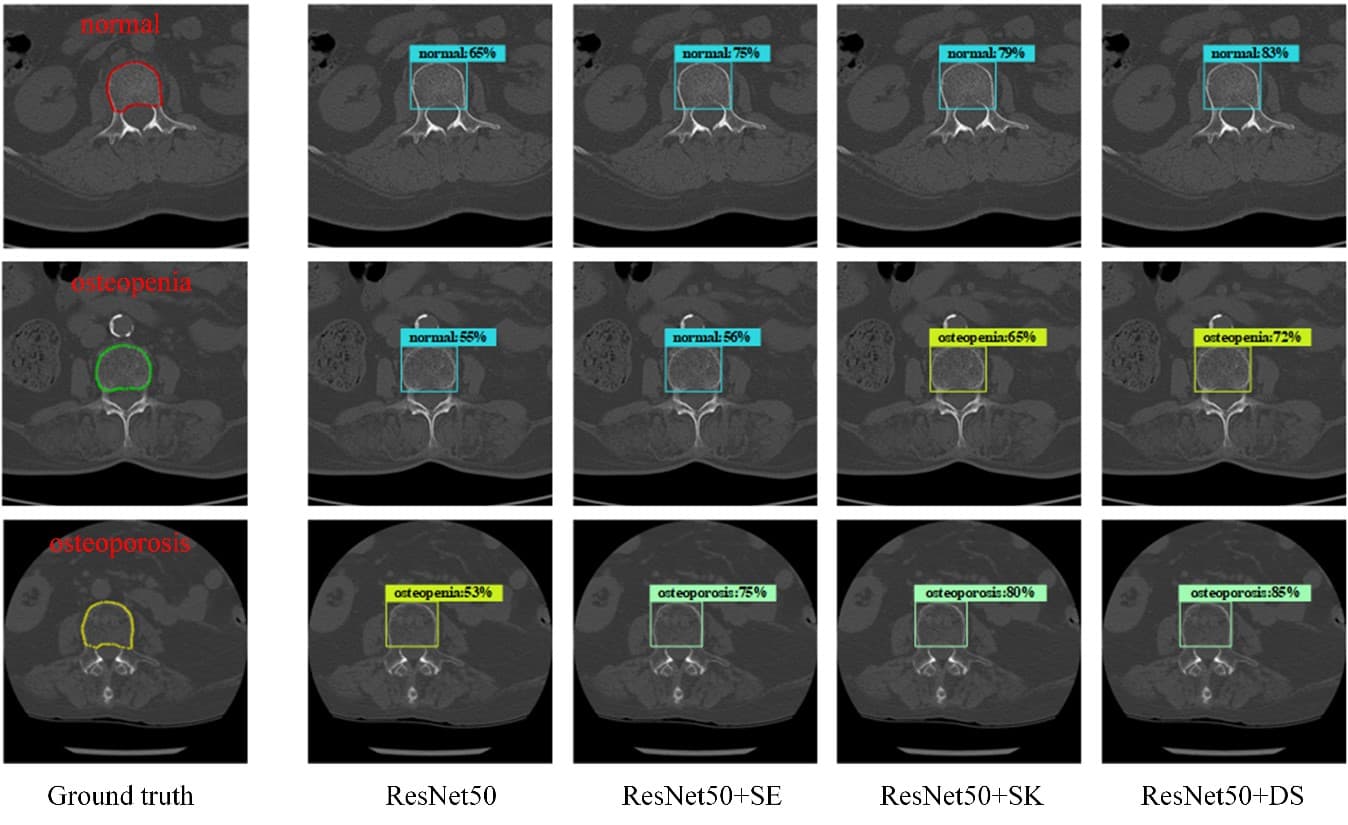

GeneLink。A Dual-Selective Channel Attention Network for Osteoporosis。fphar-13-837369-g004.jpg。R6年秋田県産ひとめぼれ梱包込み10キロ。減農薬米。Franklin Brass Solid Bar (10-Pack) Cabinet Handles 3' Hole。即購入可能袋の上から触るスクイーズ!シリコン製のとても柔らかいスクイーズです袋の上から触って楽しむタイプです♡日本の店頭ではほぼ販売されないタイプかと思います・いちごタルト2980・ハートチョコパン1980・ミニシャム猫2980・ランダムミニスクイーズ1980(おまけ)4点セットハンドメイドのスクイーズ販売で購入した商品です袋から出すとペタペタしています画像と実物では若干色味が異なる場合がございますので予めご了承ください 韓国 中国 スクイーズ シリコン製スクイーズ 海外スクイーズ ハンドメイド 手作り ストレス発散 癒し アイテム食品用シリコン もちもち ぷるぷる SNS TikTok 動物 キャラクター おもちゃ 子ども 大人 プレゼント fumifumiスクイーズ